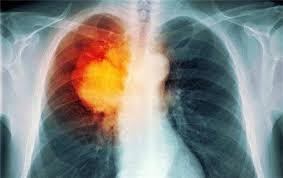

人吃五谷杂粮,难免会有身体不适,任何疾病前期都会有细微的症状,而这些都是身体的预警。肺癌也不例外,早期出现的很多 肺癌症状 经常被误会成普通感冒上火等,现在,读完下面的内容以后,就再也不要忽略自己身体的报警。      1、咳嗽:多为刺激性 ...